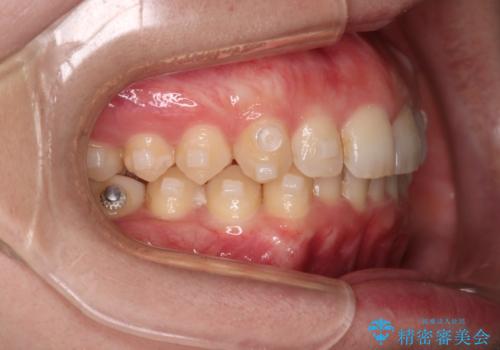

- 下の歯のがたつきを主訴に来院されました。

下の歯のがたつきと右の奥歯の噛みあわせ改善するために治療計画を立てることにしました。

右側臼歯部の咬合改善のために、臼歯部のみ部分的なワイヤー矯正を行い、咬合改善がみられてからインビザラインにて全体的な矯正を行なっていく治療計画を立てました。

噛み合わせをよくするために、ワイヤー矯正とインビザライン矯正のどちらの期間も必要な箇所にゴム掛けを行いながら治療を行いました。

下の前歯のがたつき改善にはIPR(歯と歯の間を削る処置)を行いました。

ゴム掛けを頑張っていただいたので、噛みあわせも改善され綺麗な歯並びになりました。